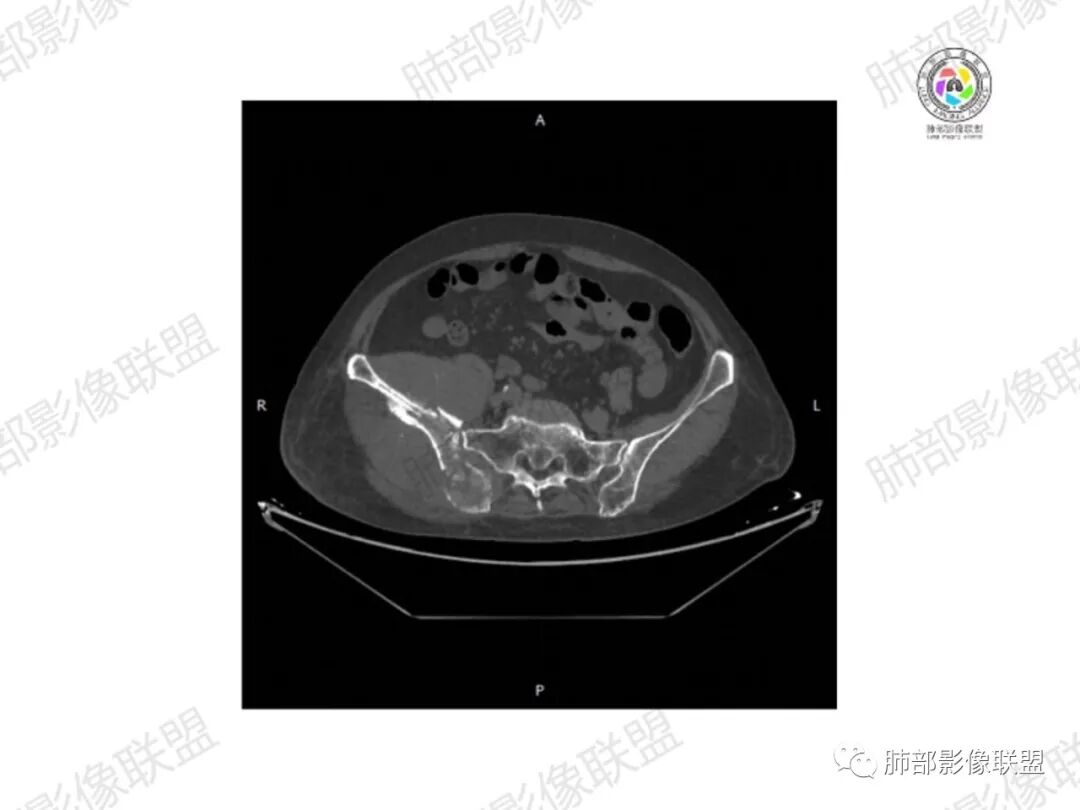

2.右髂骨轻度变形伴广泛骨质吸收破坏,边界不清且突破骨皮质。近中线区以溶骨性破坏为主,髂骨翼一侧则成骨性改变明显,骨表面见垂直骨针或花边样高密度瘤骨。

3.患骨多处皮质断裂,符合病理性骨折。注意折端可能会形成骨痂,但本例无论是形态还是部位都不符合骨痂。

4.患骨两旁(即盆骨内外)见边界不清的较大范围软组织快影,其间偶见骨化影。

1.边界不清的骨质吸收破坏,溶骨明显,骨皮质突破,软组织肿块,种种迹象表明其恶性无疑!

2.但注意这是有“成骨”的恶性骨肿瘤!我们知道老年患者的骨原发性恶性肿瘤“成骨”非常少见。少数转移瘤可为成骨型或混合型,女性患者如乳腺癌骨转移等。在男性,最典型的成骨转移是前列腺癌。

本例右侧髂骨具有较为典型的“骨肉瘤”影像学特征,有边界不清的吸收破坏、有新生骨、形成软组织肿块等等。